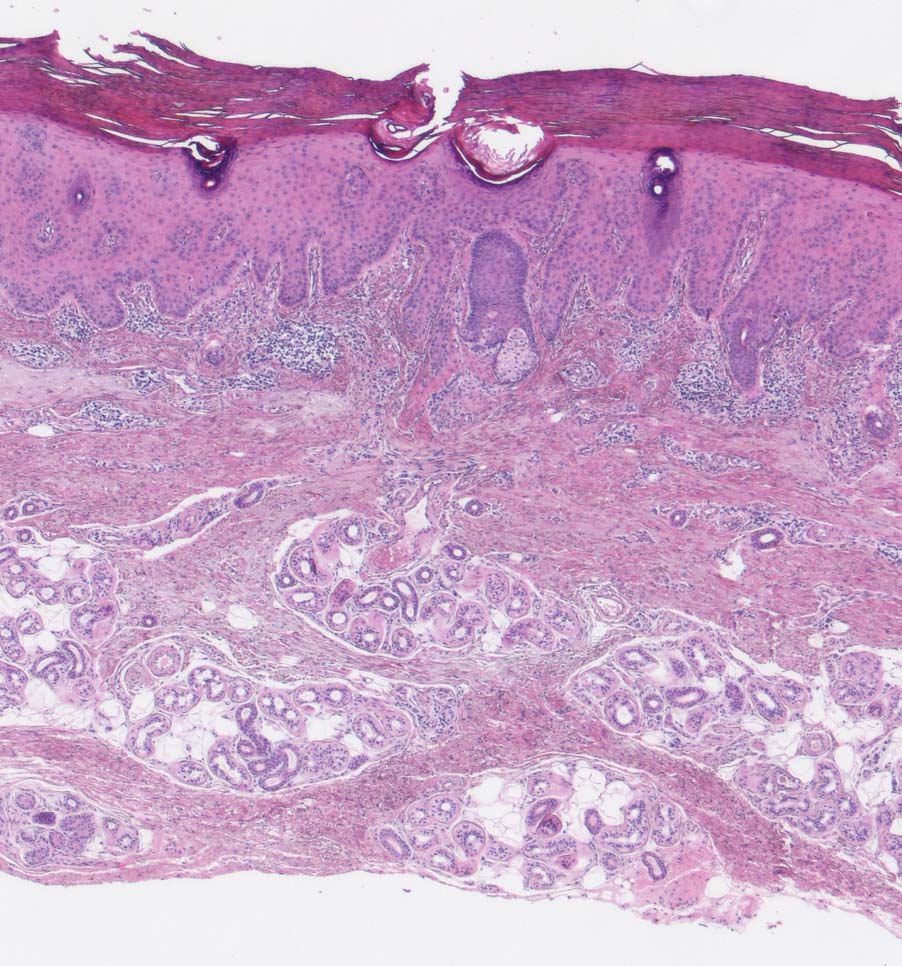

Die Epidermis zeigt obligat dysplastische Veränderungen. Die Dysplasie kann sich auf das untereste Epitheldrittel beschränken (leichte Dysplasie) oder die gesamte Epithelbreite betreffen (=bowenoide aktinische Keratose bzw. Carcinoma in situ). In der Dermis findet sich als Zeichen der chronischen UV Schädigung der Haut immer eine ausgeprägte solare Elastose. Das histologische Bild ist abgesehen von diesen zwei obligaten Befunden sehr variabel. Dyskeratotische Zellen und Mitosen finden sich häufig. Charakteristisch ist auch das Vorliegen einer alternierenden Para- und Orthokeratose, die unterschiedlich stark ausgeprägt ist. Manchmal findet man eine Atrophie der Epidermis mit schmalem Stratum corneum oder umgekehrt eine massive Hyperkeratose wie beim Cornu cutaneum. Akrosyringium und innere Abschnitte der Haarfollikel sind von den dysplastischen Veränderungen ausgespart. Die Epidermis zeigt häufig eine unregelmäßige Hyperplasie mit in das Stratum papillare reichenden Knospen. Bei Ausdehnung der Dysplasie entlang von Haarfollikeln in die Tiefe, können sich bei zu oberflächlicher Abtragung der Läsion Lokalredzidive ausbilden.

• Ausgeprägte solare Elastose (Zeichen der chronischen UV Schädigung).

• Irreguläre verruköse Akanthose der Epidermis (klinisch: Cornu cutaneum).

• Hyperparakeratotische Verhornung mit erkennbaren Kernresten in der Hornschicht.

• Epitheldysplasie: Reifungs- und Schichtungsstörung der Epidermis mit fokalem Polaritätsverlust der Keratinozyten, Atypien der Keratinozyten (hyperchromatische, pleomorphe und entrundete Zellkerne mit irregulärer Kernmembran und prominenten Nukleolen, vergrösserte Zellkerne mit hoher Kern-Plasmarelation) bis in obere Schichten der Epidermis. Dyskeratosen (hypereosinophile abgerundete Keratinozyten mit pyknotischem Zellkern als Zeichen der Verhornungsstörung). Crowding (überlappende Zellkerne).

• Adnexstrukturen (Infundibulum und Akrosyringium) sind nur oberflächlich betroffen von den dysplastischen Veränderungen.